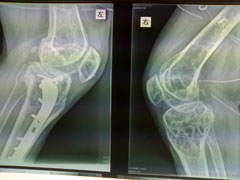

以下是引用杀毒软件在2009-7-17 11:54:00的发言:[br]骨软化症,内分泌性骨病,大骨节病均不能排除,请结合实验室检查。

以下是引用随光逐影在2009-7-17 15:12:00的发言:[br]甲状旁腺机能亢进引起多发性纤维囊性骨炎?

以下是引用zxl51642在2009-7-17 10:13:00的发言:[br]多关节骨质疏松并关节间隙狭窄,关节变形。考虑类风湿,结合病史及实验室检查(rf因子)。[br]

以下是引用dr.king在2009-7-18 20:57:00的发言:[br]甲状旁腺机能亢进引起多发性纤维囊性骨炎?进一步结合实验室检查。